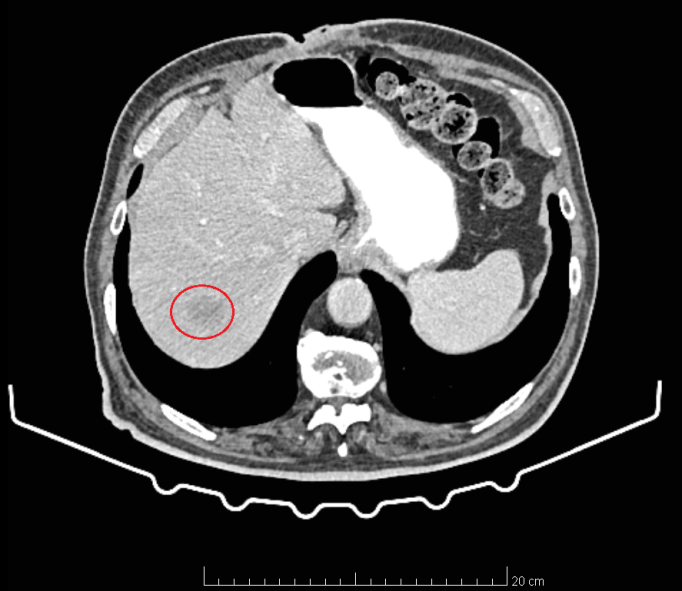

CT of the upper abdomen. Solitary metastatic focus in segment VII of the liver (Courtesy Dr. V. Penopoulos)